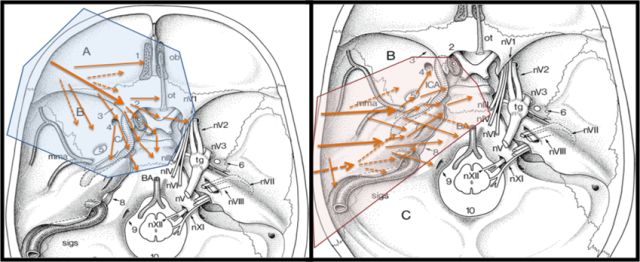

手术体位及入路

颅颈交界区显微解剖

小脑幕切迹显微解剖

前床突区域显微解剖

眶尖显微解剖